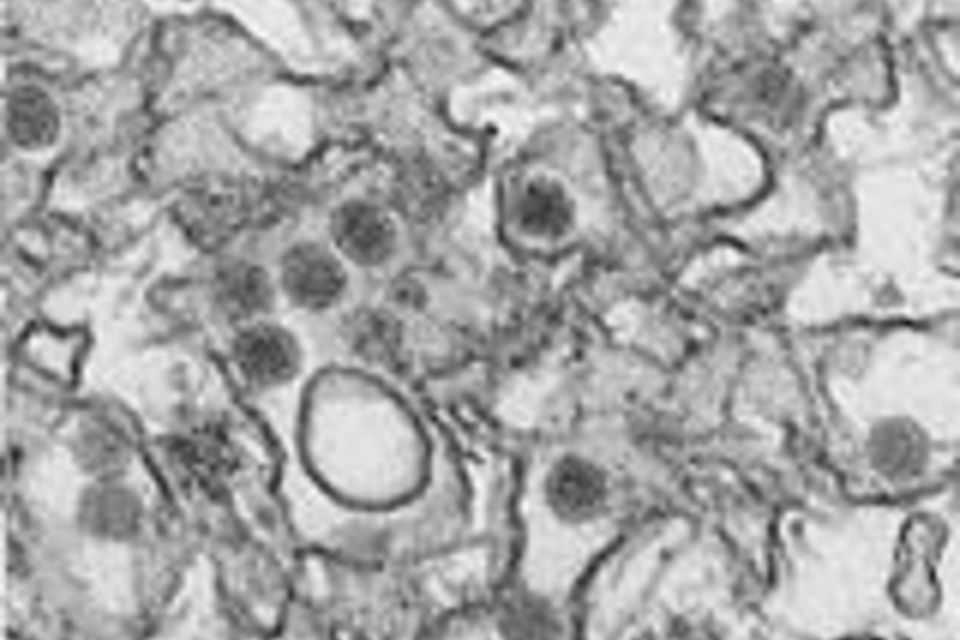

Aldrig set før: I USA har kvinde smittet mand med zika-virus

Ubeskyttet sex resulterede i usædvanlig Zika-spredning i New York, USA.

Det første dokumenterede tilfælde af overførsel af Zika-virus fra en kvinde til en mand gennem sex er blevet registret i New York. Det oplyser byens sundhedsmyndigheder fredag.